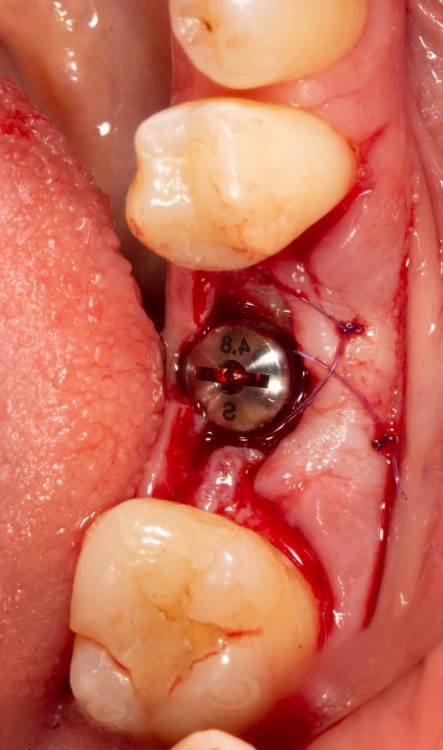

Женька Опубликовано 19 июня, 2023 Поделиться Опубликовано 19 июня, 2023 Здравствуйте, коллеги. Примерно с нового года начал ставить ТЛ имплантаты Дентиум. Что-то под заглушку (не поймал торки, представляете?). Что-то на низких формирвателях. И вот пришла пора протезирования, но отпустить к ортопеду не подготовив десну - не получается. Создал сам себе проблем, сегодня вот исправлял. Получилось неплохо? 3 Ссылка на комментарий

Женька Опубликовано 20 июня, 2023 Автор Поделиться Опубликовано 20 июня, 2023 @АнтонТЛТ мы же позиционируем платформу относительно зенита? Есть ли разница тогда, какой имплантат мы выбираем? Вообще весь смысл здесь был заложен в том, что толщина гребня была не очень. Хотелось поставить тонкий имплантат 3.6. Но рисковать тонкой платформой не хотелось, поэтому выбор пал на 4.8 платформу ТЛ и тело имплантата 3.6 1 Ссылка на комментарий